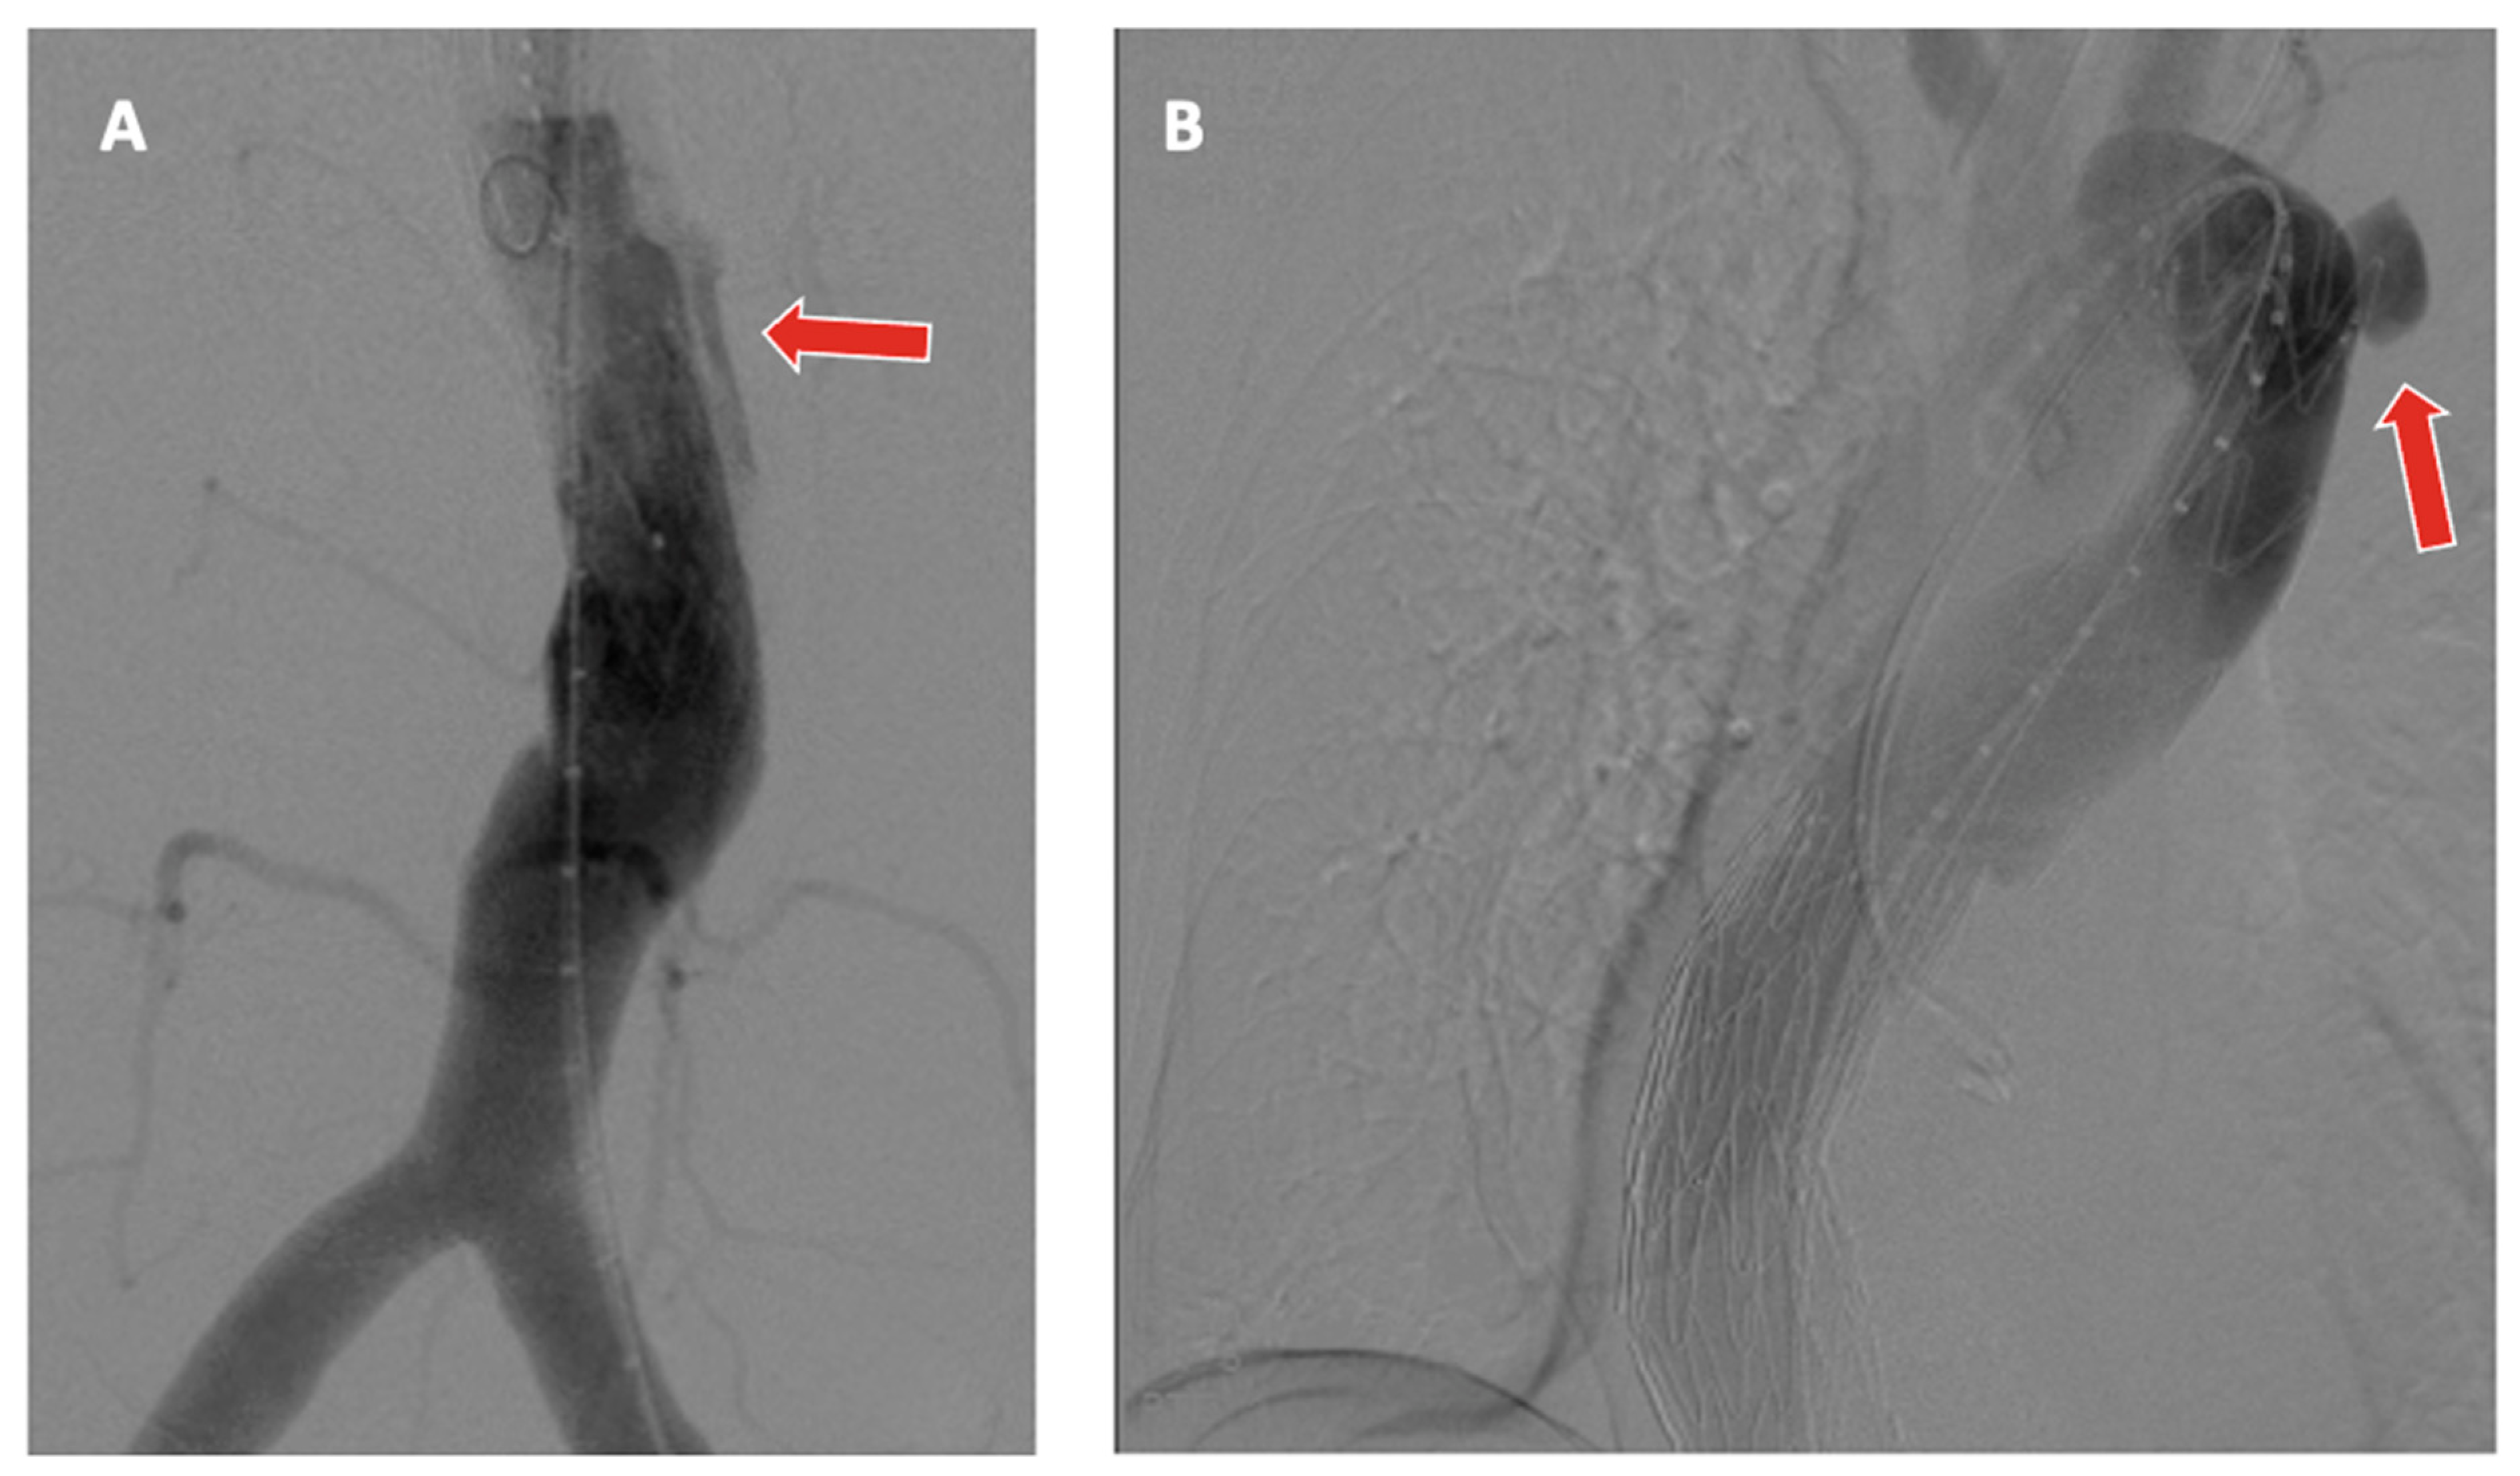

Visceral vessel cannulation, wire insertion, and placement of bridging stents represent opportunities for potentially serious complications related to F/BEVAR, such as embolization or dissection. Once the TV has been cannulated, there is a risk of injury to the artery itself, with vessel perforation, or the end-organ it supplies, especially with renal arteries (Figure 5) [39].

Figure 5.

(A,B) Distal left renal artery rupture after bridging stent deployment during a TAAA repair, as observed on selective angiography (blue arrow).